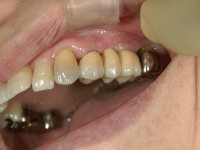

最後にクラウンを装着して、これでインプラント治療は終了となります(かぶせ物)。